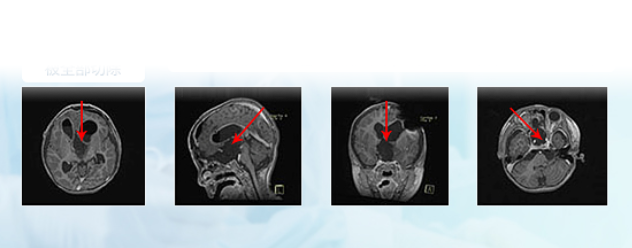

德国巴教授INI手术结果

该患儿术后病理结果显示WHO 1级,是一种低级别胶质瘤。根据美国脑胶质瘤NCCN治疗指南及临床数据统计提示,术后不需要进行放化疗等治疗(放化疗对病情控制无益,但是对身体的伤害大于获益),而且20年总体生存率87%±0.8%。